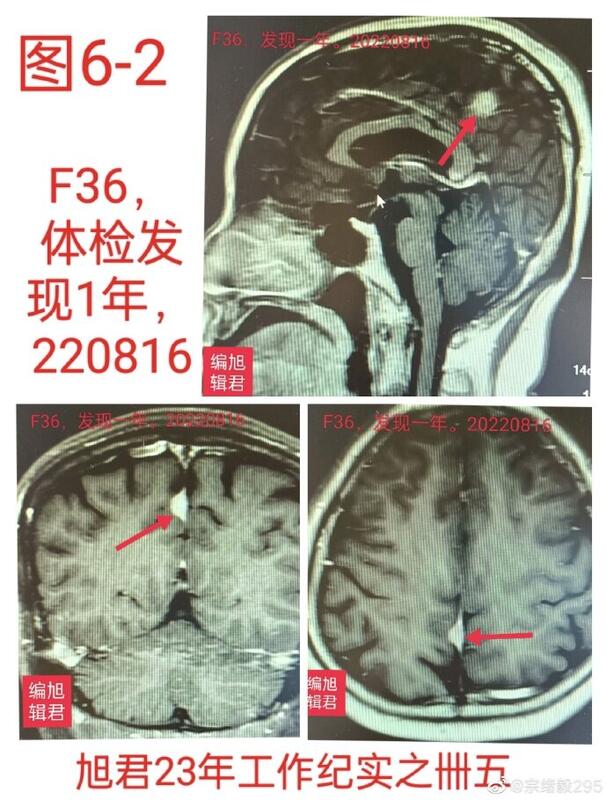

图6,1-2:某患者35岁,体检发现,观察一年复查无变化,无不适。

图6-1

图6-2